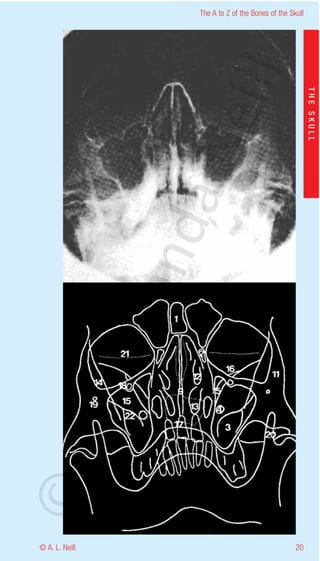

The A to Z of the Bones of the Skull

External Skull Anterior

eill

upper and lower views in detail

THE SKULL

radiology occipitomental (lower)

1           Frontal sinus

aN

2           Ethmoid sinus

3           Maxillary sinus

4           Foramen rotundum

5           Supraorbital fissure

6           Anterior clinoid process

7           Posterior clinoid process

nd

8           Petrous ridge

9           Floor of the hypophyseal fossa + upper apex of

nasal cavity adjacent to nasal sinuses

10          Crista galli

11          Frontal process of zygoma

ma

12          Middle concha - turbinate

13          Inferior concha - turbinate

14          Lateral border of Greater wing of sphenoid

15          Greater wing of sphenoid

16          Lesser wing of sphenoid

rA

17          Hard palate

18          Infraorbital foramen

19          Zygomaticofacial foramen

20          Coronoid process of the mandible

21          Soft tissue of lower lid

©D

22          Pterygoid plates of the sphenoid